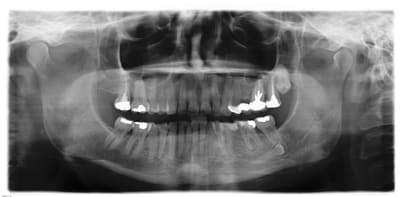

Pano 35 pth9yj - Eugenol